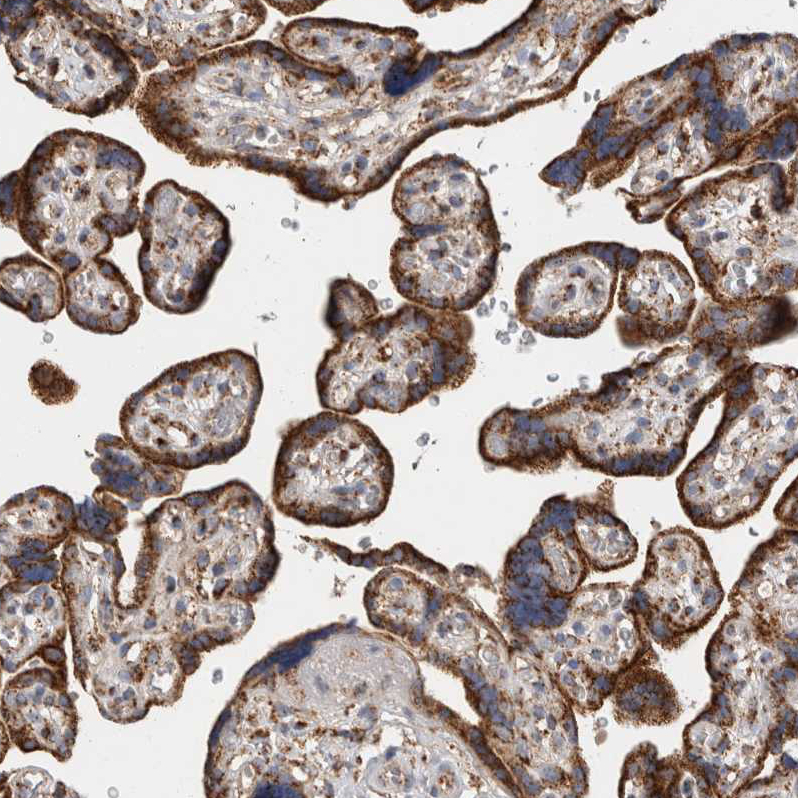

Immunohistochemical staining of human kidney, lower gastrointestinal, placenta and testis using Anti-IARS2 antibody HPA024594 (A) shows similar protein distribution across tissues to independent antibody HPA024212 (B).